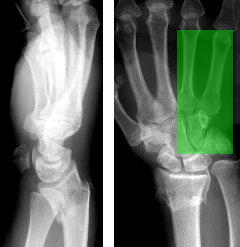

MedVistaGym comprises a set of verifiable medical VQA tasks that demand grounded, multi-step reasoning over visual inputs and intermediate evidence. These tasks span diverse diagnostic scenarios, including clinical perception, lesion-level evidence localization, subtle abnormality detection, and diagnosis-oriented evidence aggregation, where generating reliable answers requires calling external tool support. The training data in MedVistaGym is organized along two complementary axes. (1) Radiology VQA, covering cross-sectional and projection imaging, includes VQA-RAD Lau et al. (2018), which focuses on anatomy and finding recognition in X-ray, CT, and MRI images, and SLAKE Liu et al. (2021), a knowledge-aware dataset with clinically grounded questions over diverse radiology images. (2) Pathology VQA, covering microscopy and histopathology, includes PathVQA He et al. (2020), which emphasizes cellular morphology and tissue patterns. More details are provided in Appendix A.2.